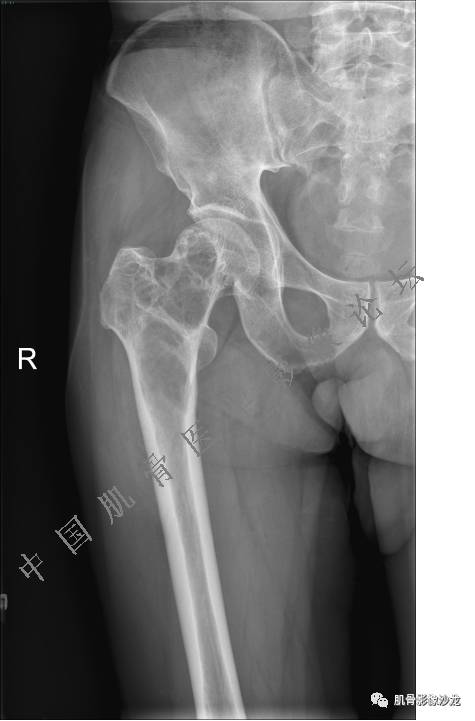

主诉:右侧股骨近端持续疼痛1月余

现病史:1个月前因天气转冷突然右侧股骨疼痛,无乏力麻木,遂就诊于当地医院X线检查发现右股骨异常密度,为进一步诊治来我院。

既往史:高血压史。余无特殊。